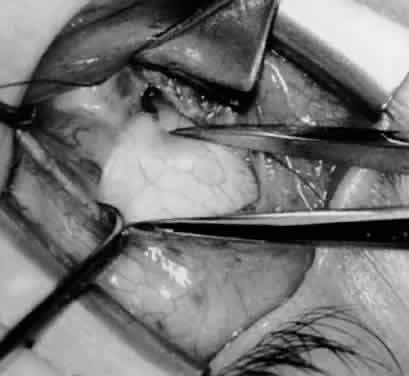

Fig. 13. The inferior oblique muscle is sectioned from the globe. A preplaced 6-0 Vicryl suture is attached to the insertion.

Fig. 14. The inferior temporal vortex vein, 8 mm posterior to the temporal insertion of the inferior rectus muscle, is held on a Green muscle hook.

Fig. 15. The placement of sutures within the sclera for a recession procedure of 10 mm. The anterior suture is placed 3 mm temporal and 2 mm posterior to the lateral insertion of the inferior rectus muscle, and the posterior suture is placed 3 mm further posteriorly.

Fig. 16. Two sutures straddle the inferior temporal vortex vein insertion for a 14-mm recession procedure.